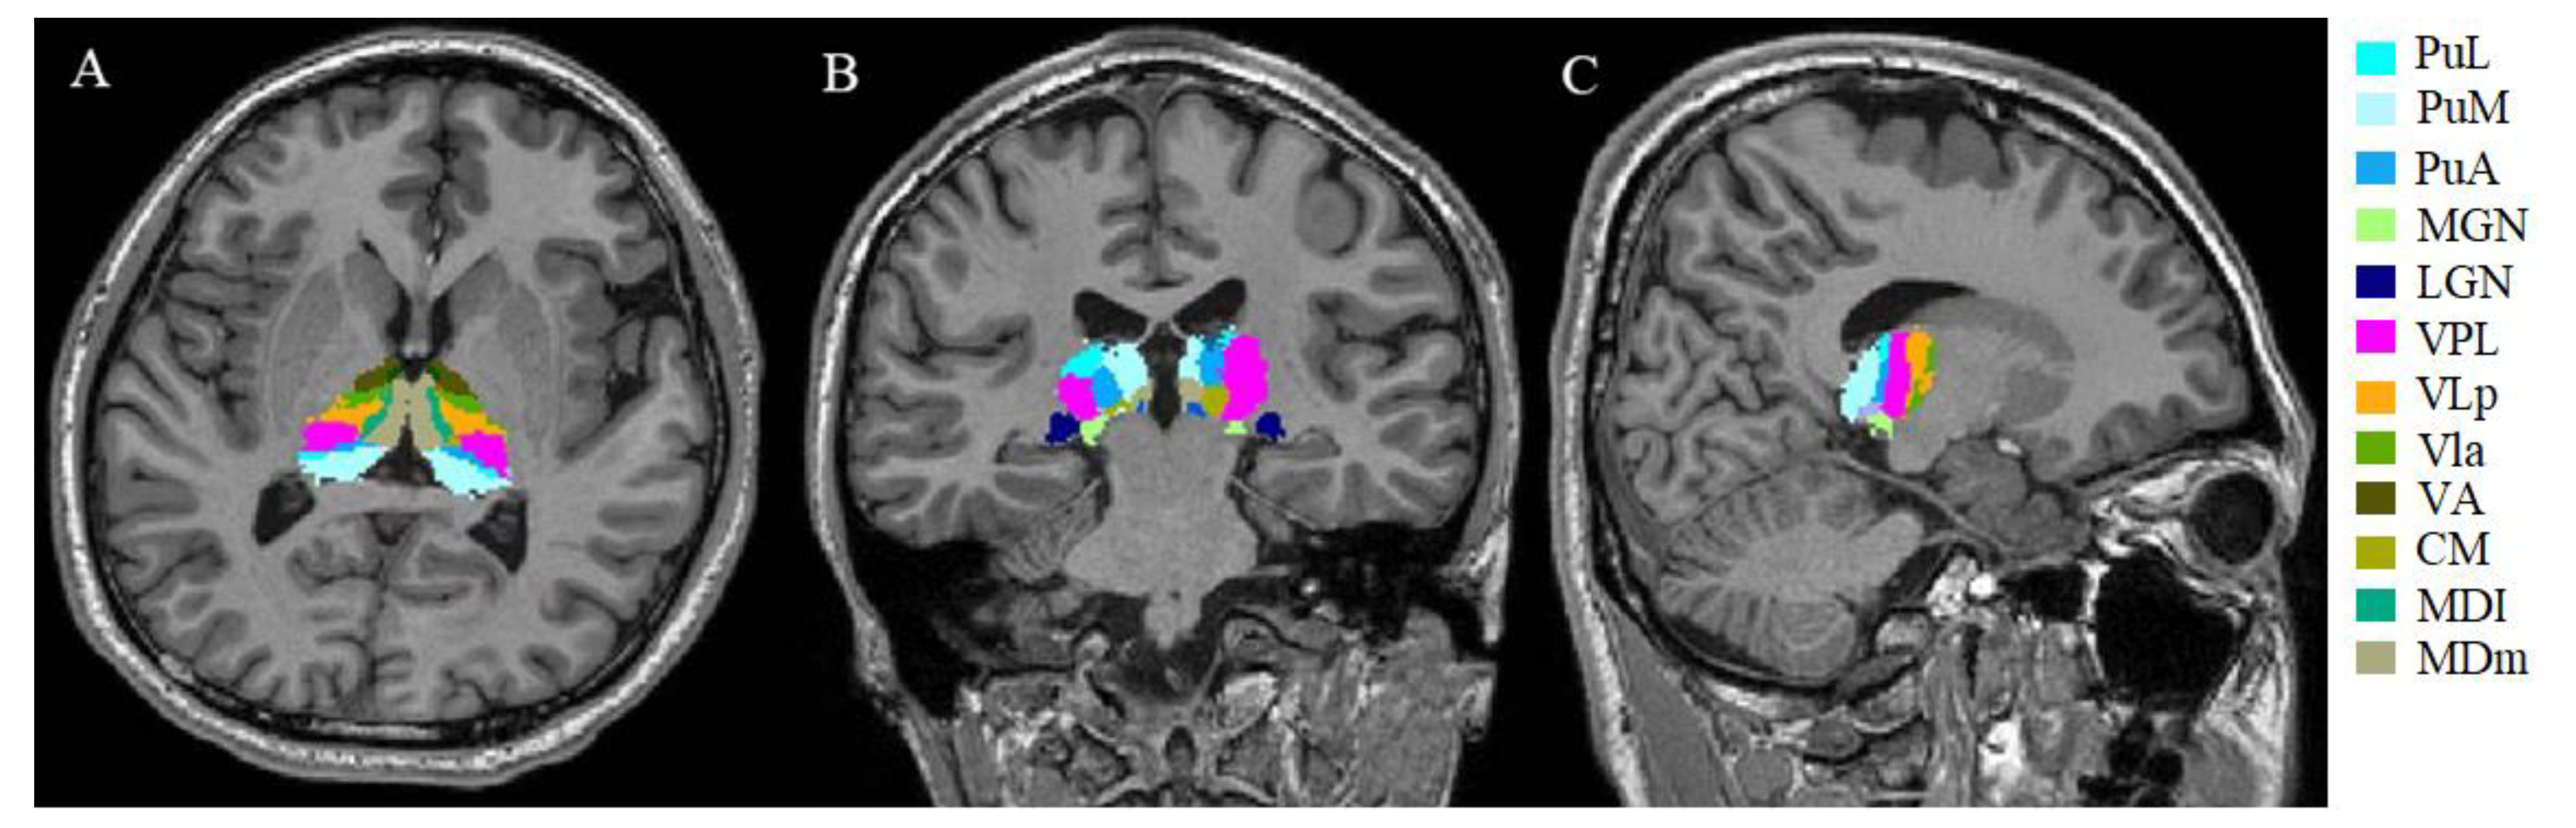

2.5. Thalamic Nuclei Volume Analysis

- Iglesias, J.E.; Insausti, R.; Lerma-Usabiaga, G.; Bocchetta, M.; Van Leemput, K.; Greve, D.N.; van der Kouwe, A.; Fischl, B.; Caballero-Gaudes, C.; Paz-Alonso, P.M. A probabilistic atlas of the human thalamic nuclei combining ex vivo MRI and histology. NeuroImage 2018, 183, 314–326. [Google Scholar] [CrossRef]